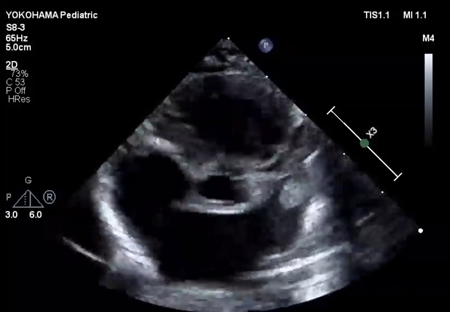

LV ejection fraction was down to 40% with moderate mitral regurgitation, whereas RV contractility was preserved. The biventricular volumes seemed well-balanced, and the LV end-diastolic diameter (15.9 mm) was within the normal range. Systolic RV pressure was estimated as 70 mmHg by regurgitation flow across the tricuspid valve (velocity 4.1 m/s), indicating persistent pulmonary hypertension. The ductus arteriosus had already closed. The foramen ovale (FO) was patent with very little blood flow through (Fig. 1A). The left atrium (LA) was dilated and non-contractile (Fig. 1B, Supplementary Video S1). Echocardiography showed a highly echogenic mass measuring 10×5 mm in the LA appendage, which was not mobile. The mass was suspected to be a thrombus (Fig. 1C, Supplementary Video S2). Blood tests indicated a high B-type natriuretic peptide (BNP) level (1,102.8 pg/mL) and a mildly elevated D-dimer level (2.27 µg/mL). There was no decrease in platelet count (279×103 /µL) or increase in clotting time (prothrombin time/international normalized ratio: 1.05, activated partial thromboplastin clotting time [APTT]: 29.9 s). The levels of fibrinogen (326 mg/dL), antithrombin-III (65%), protein C (35%), and protein S (68%) were within normal limits for neonates. There was no maternal history of systemic lupus erythematosus or antiphospholipid antibody syndrome, which could have affected neonatal formation of intracardiac thrombi.

Fig. 1 Echocardiographic findings

(A) Echocardiography at the time of admission (subcostal view) showed only a small slit-like blood flow across the foramen ovale. (B) Echocardiography on admission (four-chamber view) showed a dilated left atrium with an end-systolic volume of 4.0 mL. The left ventricular end-diastolic diameter was normal (15.9 mm). The left ventricular contraction was mildly reduced, with an ejection fraction of 40%. (C) Echocardiography on admission (short axis view) showed a highly echogenic and non-mobile mass (white *) of 10 mm ×5 mm in the left atrial appendage. (D) Echocardiography on day 9 showed improvement in left ventricular contractility. Atrial size had become normal, with a left atrial end-systolic volume of 2.1 mL. LA, left atrium; RA, right atrium.

We administered diuretics as well as continuous infusion of olprinone and unfractionated heparin. Continuous infusion of heparin was started at 10 U/kg/hr and gradually increased to 20 U/kg/hr, but the APTT was only slightly prolonged to 36.0 seconds on day 9. Daily echocardiography showed gradual improvement in LV function. Olprinone and diuretics were discontinued by day 9, because the LV ejection fraction improved to 65% and the LA size normalized (Fig. 1D, Supplementary Video S3). Marked mobility of the mass appeared in parallel with the restoration of LA contractility on day 10 (Supplementary Video S4). We performed a surgical thrombectomy on cardiopulmonary bypass so as to avoid systemic embolism. A white structure adhering to the LA appendage was excised (Fig. 2A), and pathological diagnosis was a calcified thrombus (Fig. 2B). The postoperative course was uneventful. Low-dose aspirin was started on the 3rd postoperative day. The patient was followed up on an outpatient basis, and aspirin was discontinued at 4 months postoperatively. At the time of this publication, the patient is 2 years old, and she has experienced no recurrent clots or embolic episode thus far.